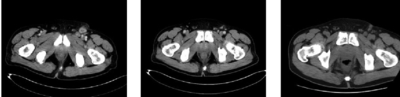

輔助檢查血常規(guī)、尿常規(guī)、肝功能、腎功能均顯示正常。大便潛血陽性。腫瘤標(biāo)志物:癌胚抗原(CEA)18.33ng/ml,糖類抗原(CA)19-9、CA125、CA242、CA72-4均正常。腹股溝淋巴結(jié)B超示左側(cè)腹股溝多發(fā)淋巴結(jié)腫大,較大者5.8cm×2.5cm,形態(tài)欠規(guī)則,轉(zhuǎn)移不除外。胸腹盆增強(qiáng)CT(圖2a)示直腸壁局限性增厚,鄰近脂肪間隙模糊,周圍筋膜未見明顯增厚,符合直腸癌改變;左側(cè)盆腔內(nèi)及左側(cè)腹股溝多發(fā)腫大淋巴結(jié),轉(zhuǎn)移可能。全身骨顯像未見明顯異常。